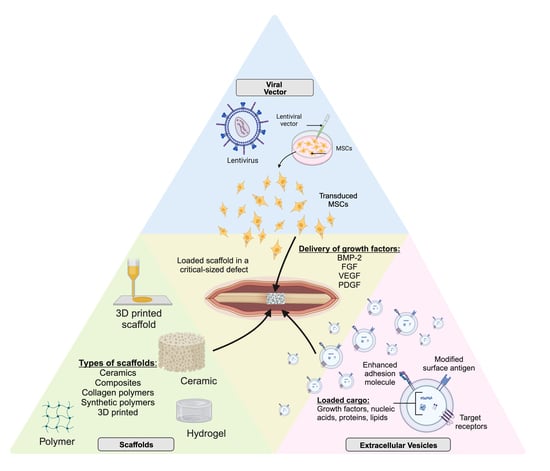

2. Carriers of Bone Morphogenetic Protein and Other Growth Factors

3. Extracellular Vesicles

4. Role of Regional Gene Therapy in Growth Factor Delivery

4.4. Role of Scaffolds in Gene Therapy